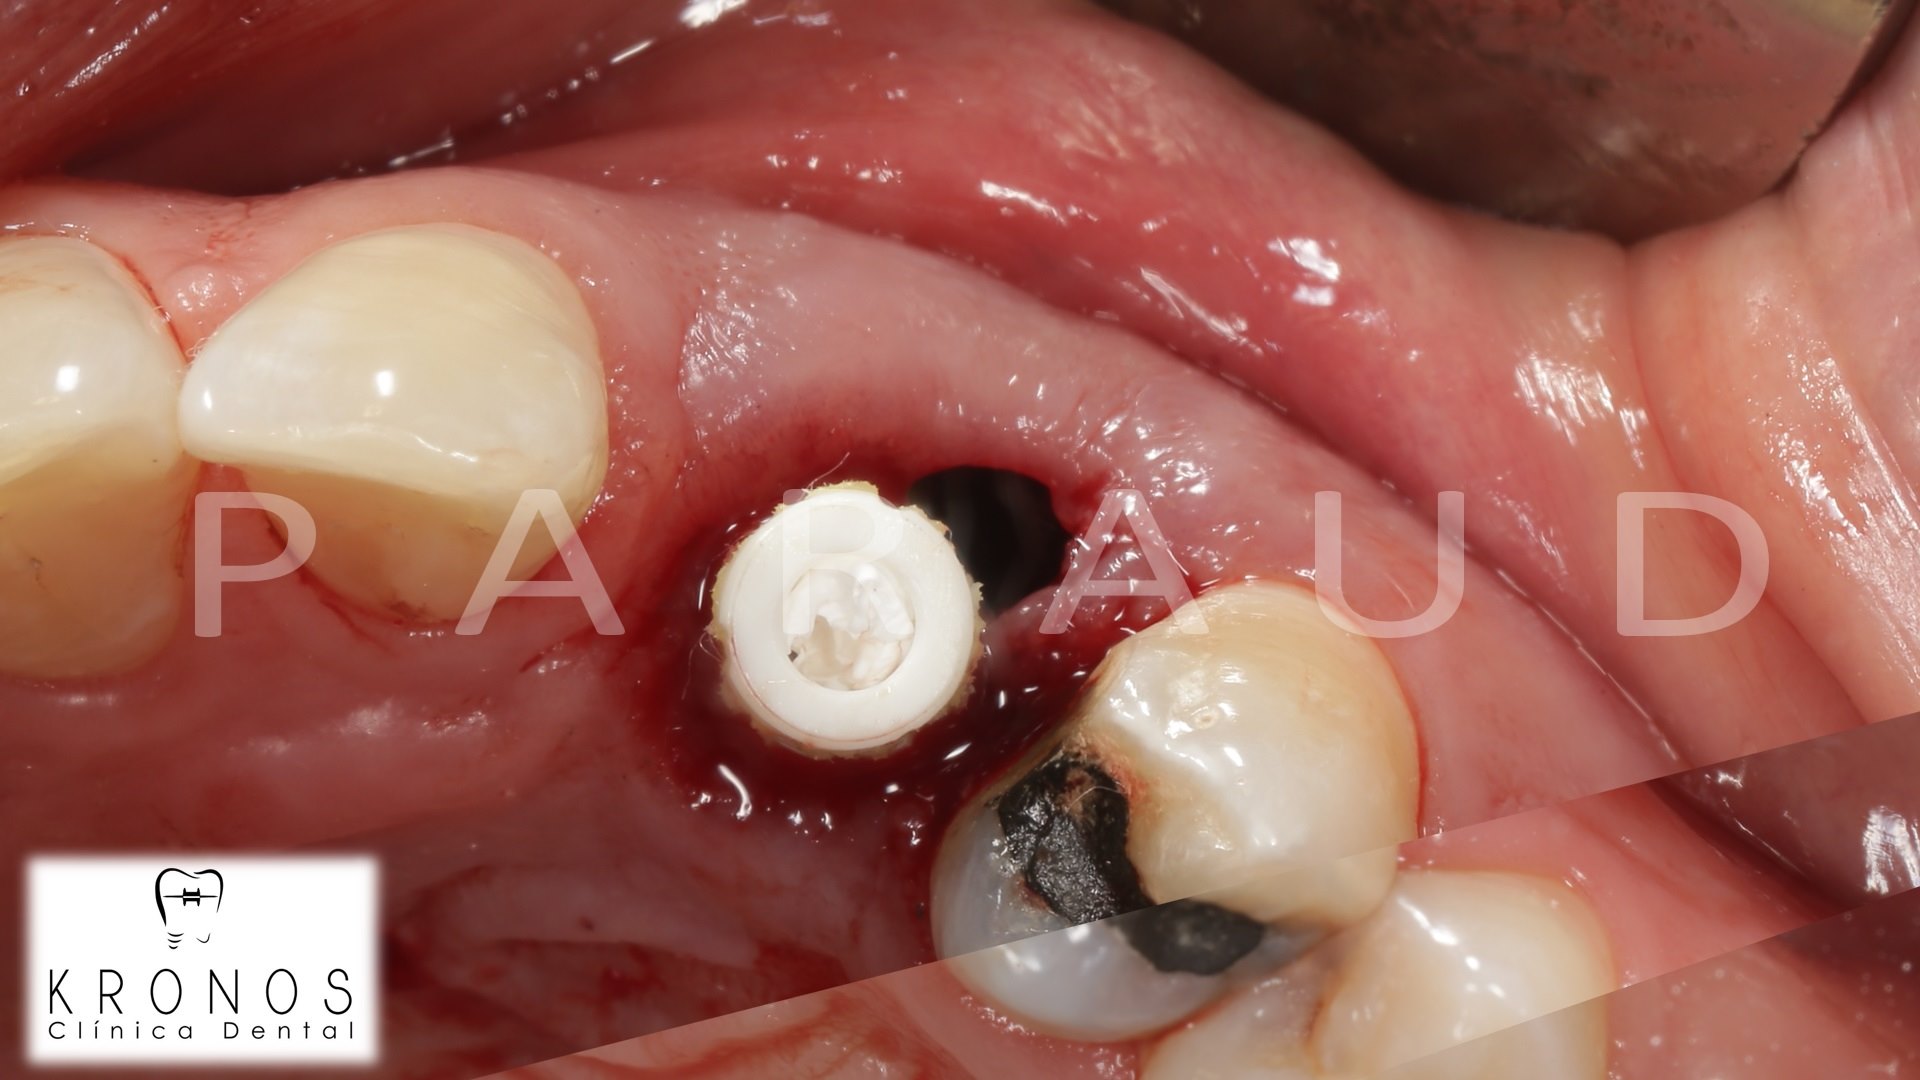

Clinical case: AnyRidge immediate loading

- Courtesy of Dr. Andres Paraud Freixas, Chile -

AnyRidge, ISQ value, initial stability, immediate loading, KnifeThread, maxillary anterior, Mega ISQ, Dr. Andres Paraud Freixas

AnyRidge implant system, Mega ISQ, Digital prosthesis